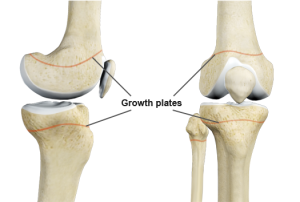

Human height depends on the activity of growth plates — the cartilage areas at the ends of long bones (such as the femur and tibia). When these plates close and harden into bone, height growth stops. According to research from the Journal of Clinical Endocrinology, growth plate closure usually occurs at:

Understanding at what age people stop growing taller is the first step to taking action before the growth plates close—especially during the golden stage between ages 10 and 18.

- Bone X-ray: Doctors can use X-rays to check whether the growth plates remain open or have closed.

If the child’s growth plates are still active (usually before age 18), this is the ideal time to apply methods that help optimize height growth.